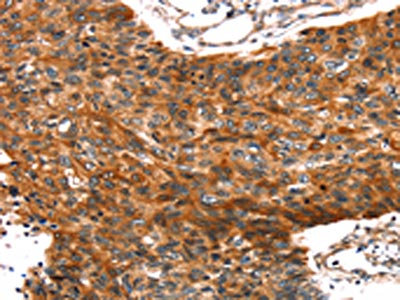

The image on the left is immunohistochemistry of paraffin-embedded Human esophagus cancer tissue using CSB-PA992772(TRIM69 Antibody) at dilution 1/40, on the right is treated with fusion protein. (Original magnification: ×200)

The image on the left is immunohistochemistry of paraffin-embedded Human prostate cancer tissue using CSB-PA992772(TRIM69 Antibody) at dilution 1/40, on the right is treated with fusion protein. (Original magnification: ×200)